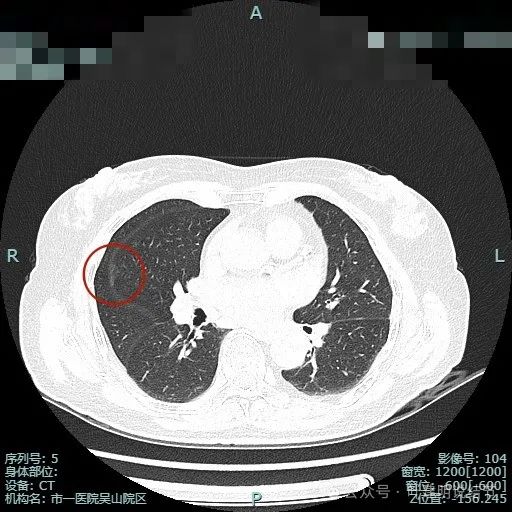

实性小肺癌只做了楔形切除,术后病理高危低分化,需要升级手术或术后辅助治疗吗?

病史摘要36 岁女性,7 月初嗓子肿 1 周后咳嗽不止、气道不适。8 月 9 日于某市人民医院呼吸科就诊,胸部平扫 CT 发现左肺上叶尖 10mm×8mm 实性结节;8 月 11 日至某市中心医院胸外科行左肺靶扫描检查,医生建议手术;8 月 13 日回某市人民医院胸外科,医生建议观察,患者计划 10 月或 11 月单位体检时再做 CT,期间服用盐酸莫西沙星及中药调理。 诊